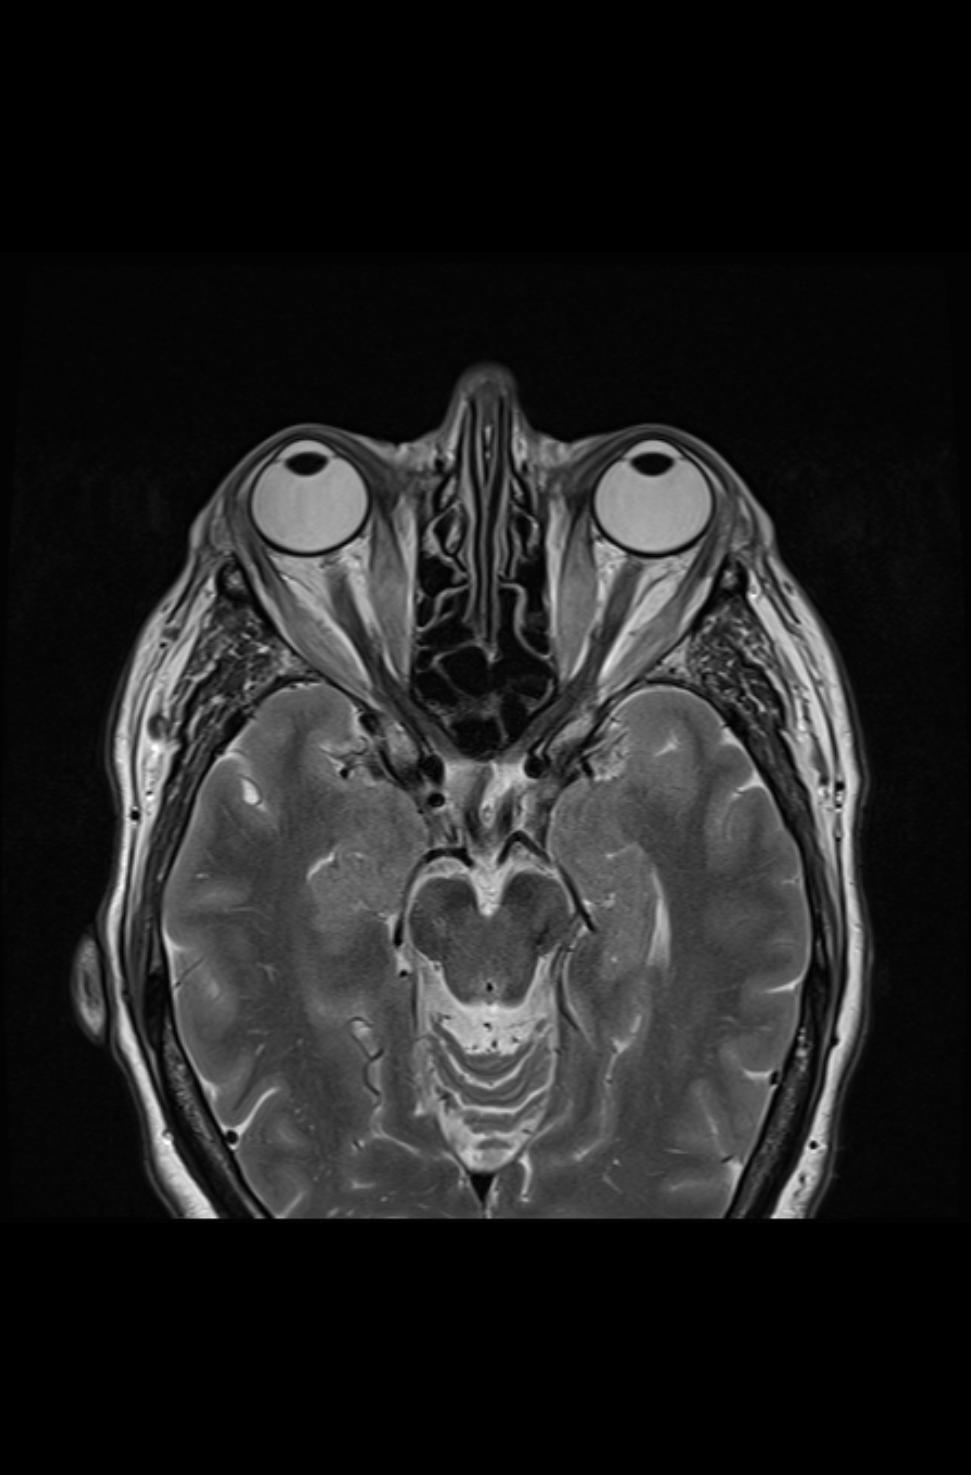

Es zeigen sich die typischen Verdickungen der Muskelbäuche der äußeren Augenmuskeln und ein Exopthalmus (Bild 3-3). In der koronaren, T2-gewichteten Sequenz mit Unterdrückung des Fettsignals (Fettsättigung) zeigt sich ein ausgeprägter Befund der endokrinen Orbitopathie mit Beteilung der Rectus-Muskeln beider Orbitae und einer Beteiligung des Musculus obliquus superior beidseits. Zusätzlich ist ein Ödem im Musculus rectus inferior beidseits, im Musculus rectus lateralis rechts, im Musculus rectus medialis links und im Musculus obliquus superior rechts abgrenzbar (Bild 3-1), welches auf eine akute entzündliche Aktivität deutet.